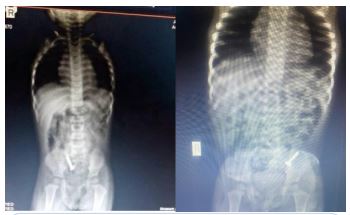

She presented with a plain abdominal radiograph which showed a FB (nail) in the body of the stomach (Figure 1) This was done about 6 hours prior to the presentation at our facility. A repeat radiograph done at the presentation showed the FB (nail) at the region of the terminal ileum (Figure 2). She was commenced on nil per oral, intravenous fluids and monitoring (clinical and radiological). She had two additional plain abdominal radiographs, (Figure 3, 24 hours on admission) and (Figure 4, on day 3). The vital signs remained stable and the abdominal examinations remained equivocal throughout the period of admission. She was discharged following a repeat radiograph which showed no evidence of FB in the GIT.

Figure 1: AP view of plain abdominal radiograph (6 hours prior to presentation).